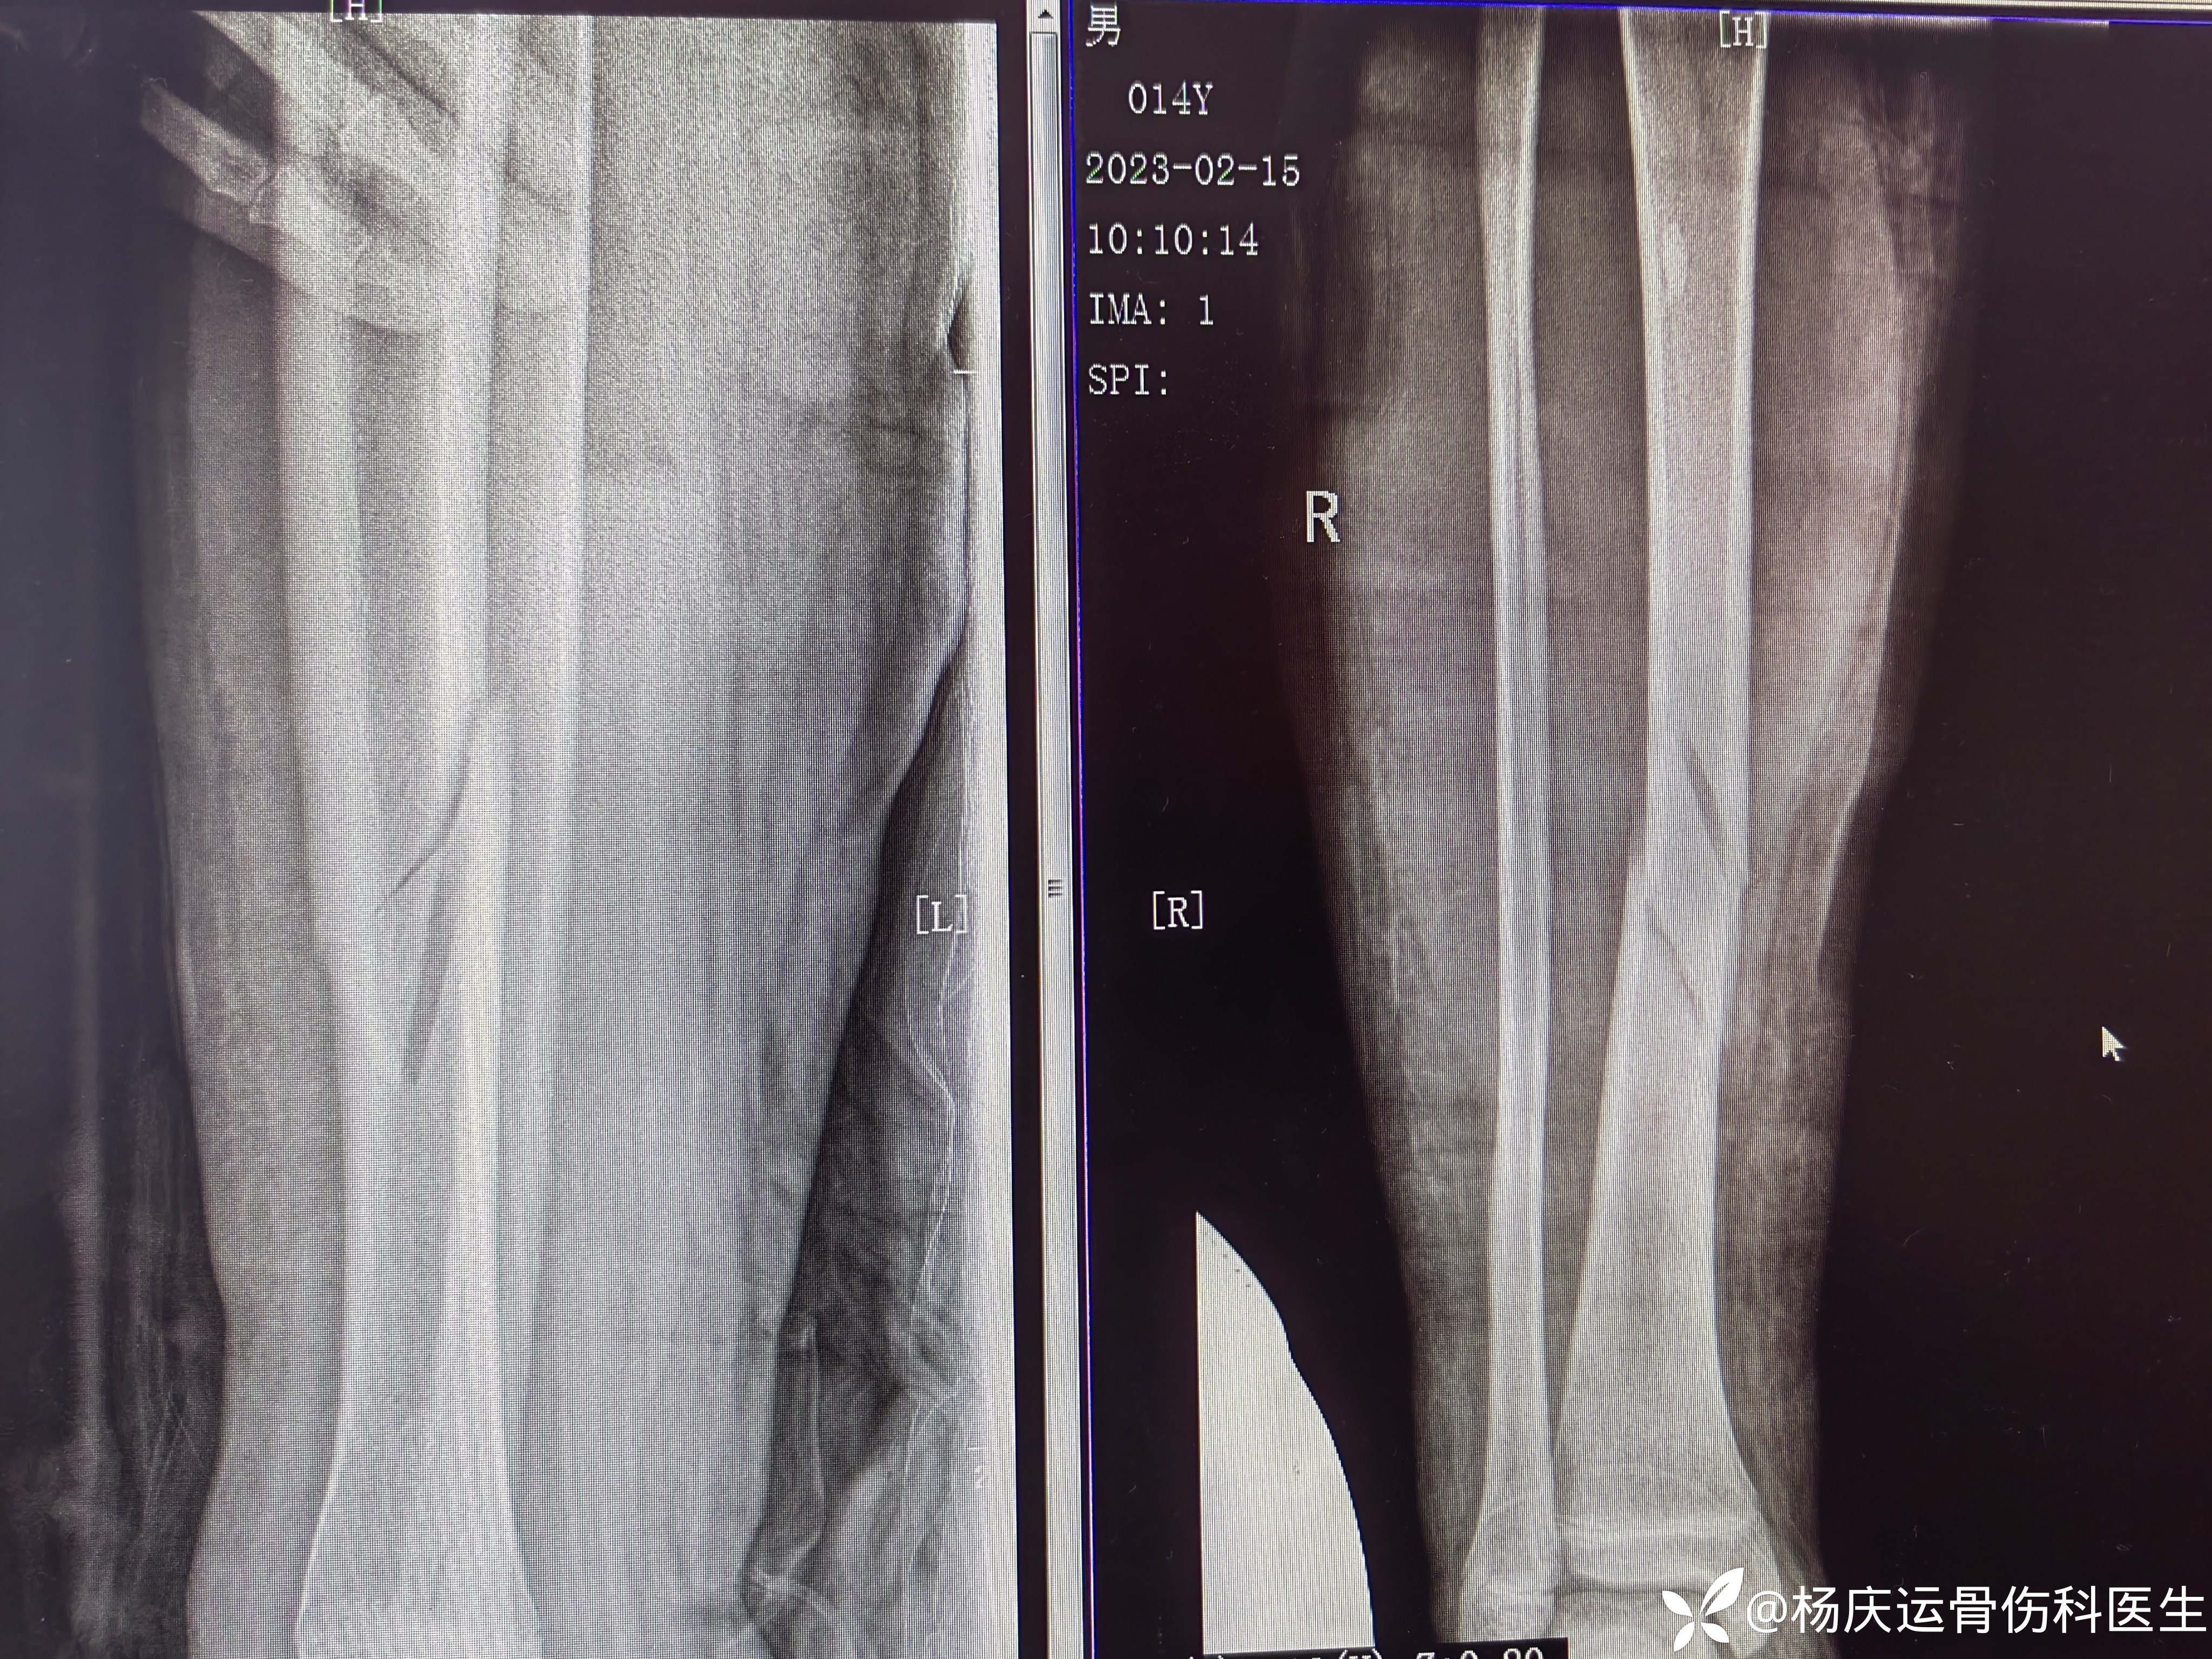

夹板外固定后

1月复查,骨折移位,力线尚可。